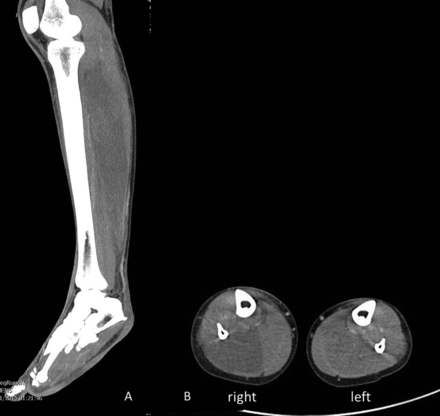

Al ser trasladada al Hospital Royal Adelaide, el doctor Thonas Kimber atendió el caso, y aseguró que nunca había visto este tipo de daño en los nervios y músculos de las pantorrillas por usar este tipo de prendas.

Por tal motivo desde el lunes pasado el doctor Kimber publicó junto a un grupo de especialistas, en la revitsta Jornal of Neurology, los efectos negativos de usar pantalones demasiado ajustados, entre los que destacan lesiones en ingles, testículos y hasta la lesión de nervios en la parte baja de la pierna, así como daños en los músculos.

El doctor Kimber explicó que al realizar sentadillas o estar de cuclillas por mucho tiempo, el suministro de sangre no viaja de forma adecuada a las pantorrillas, por lo que estas se entumecen, y de forma prolongada provoca daños en los nervios, como en el caso de australiana, quien además empeoró la situación al usar pantalones ajustados.